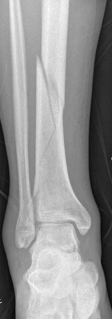

Tibial shaft fracture extending into the plafond—plate fixation Case description A 26-year-old man fell from …

Tibial shaft fracture extending into the plafond—intramedullary fixation Case description a A 25-year-old wom…